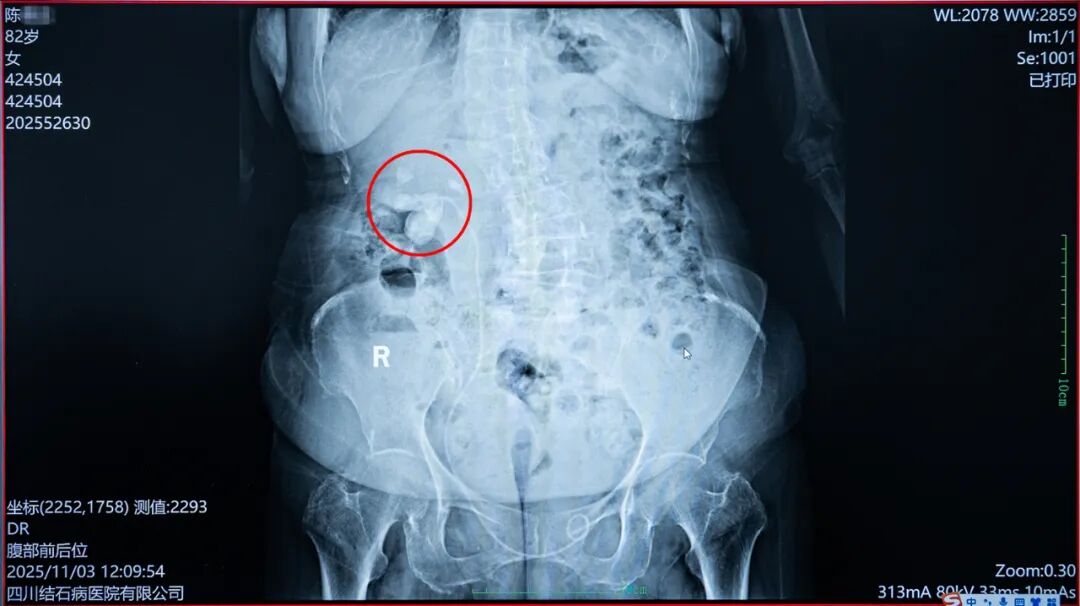

但令人遗憾的是,由于陈奶奶肾脏内结石负荷过大,且此前存在严重感染,虽经过前期治疗有所控制,但长时间手术仍可能导致感染扩散、加重身体负担,甚至引发多种并发症,给患者带来极大风险。为了确保患者安全,常立高教授当机立断,决定暂停此次手术,待陈奶奶身体进一步恢复后,再通过二期手术取出剩余结石。

△第一期手术后